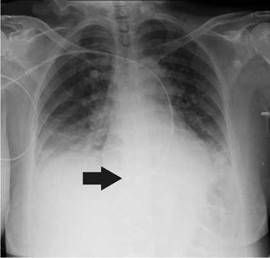

She was diagnosed with cardiogenic shock secondary to non-ST elevation acute myocardial infarction and sinus bradycardia. The initial management in the emergency room, therefore, included dual antiplatelet therapy, anticoagulation, norepinephrine, and dopamine. Then, the patient was transferred to the intensive care unit where a transvenous pacemaker was implanted using the right subclavian anatomical approach with adequate return and no suitable capture. A control chest radiography was performed which revealed no pneumothorax and hemothorax but evidenced the extreme of the pacemaker on the left atrium (figure 1). The pacemaker was considered to be poorly located, so a new one was placed through the left subclavian anatomical approach without complications and adequate capture. However, the team suspected a vascular malformation in the control chest radiograph because the extreme part of the pacemaker was located on the right ventricle (figure 2).